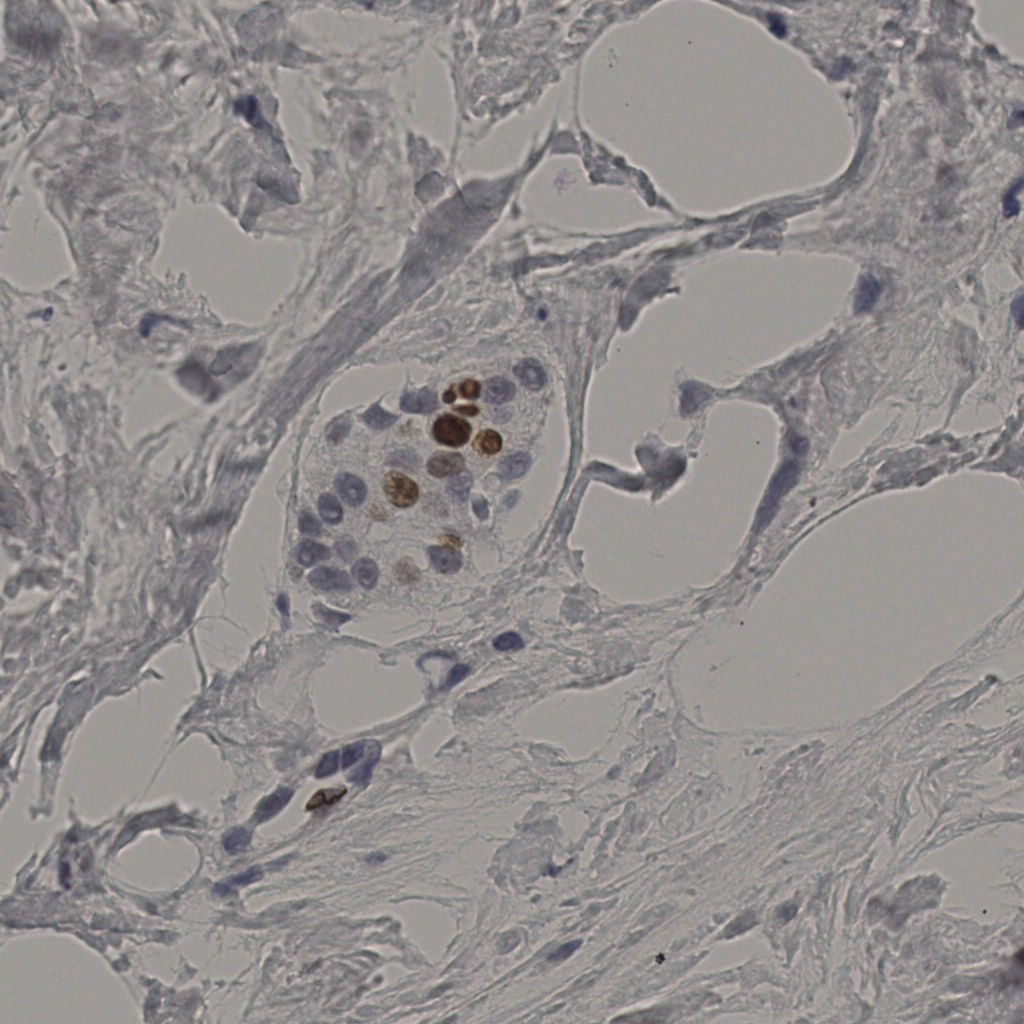

5.31%

Ki67 指数

阴 19502 阳 1093